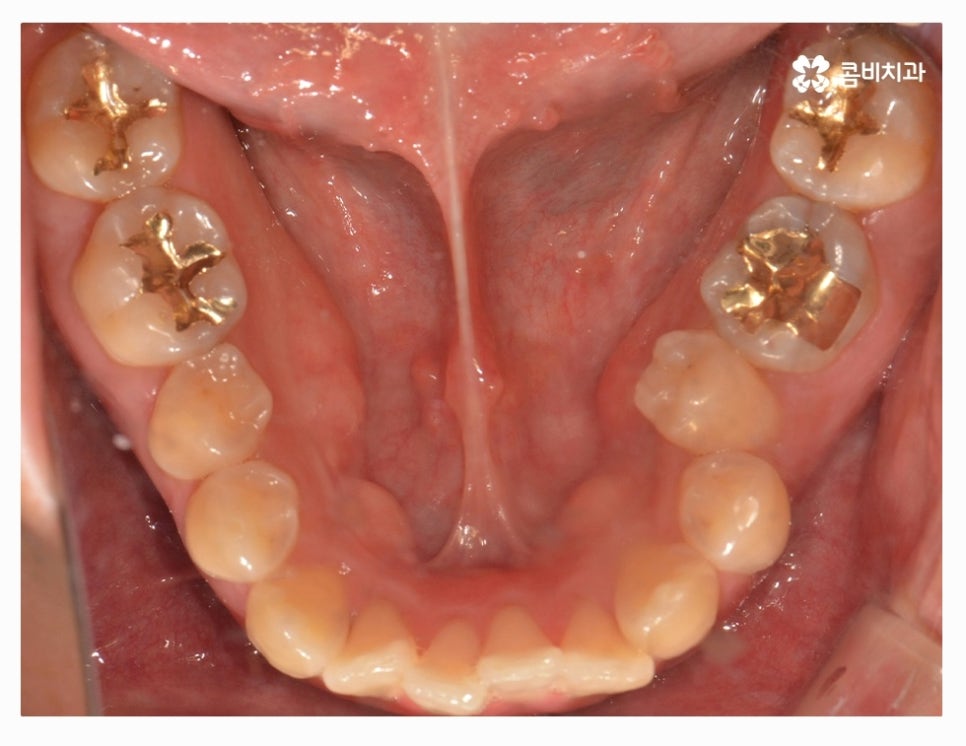

오늘 소개드릴 환자분은 윗니와 아랫니가 제대로 맞물리지 않는

부정교합 사례이며 클리피씨교정을 통해서 치료가 진행된 사례라고 할 수 있어요.